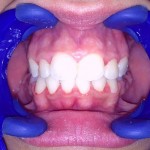

Este é um caso mais simples de se fazer e com um valor (custo-benefício) bastante cómodo.São somente 4 implantes na arcada inferior suportando uma barra sobre a qual será transferido em parte o esforço mastigatório. É confeccionada em RESINA como uma prótese total convencional.